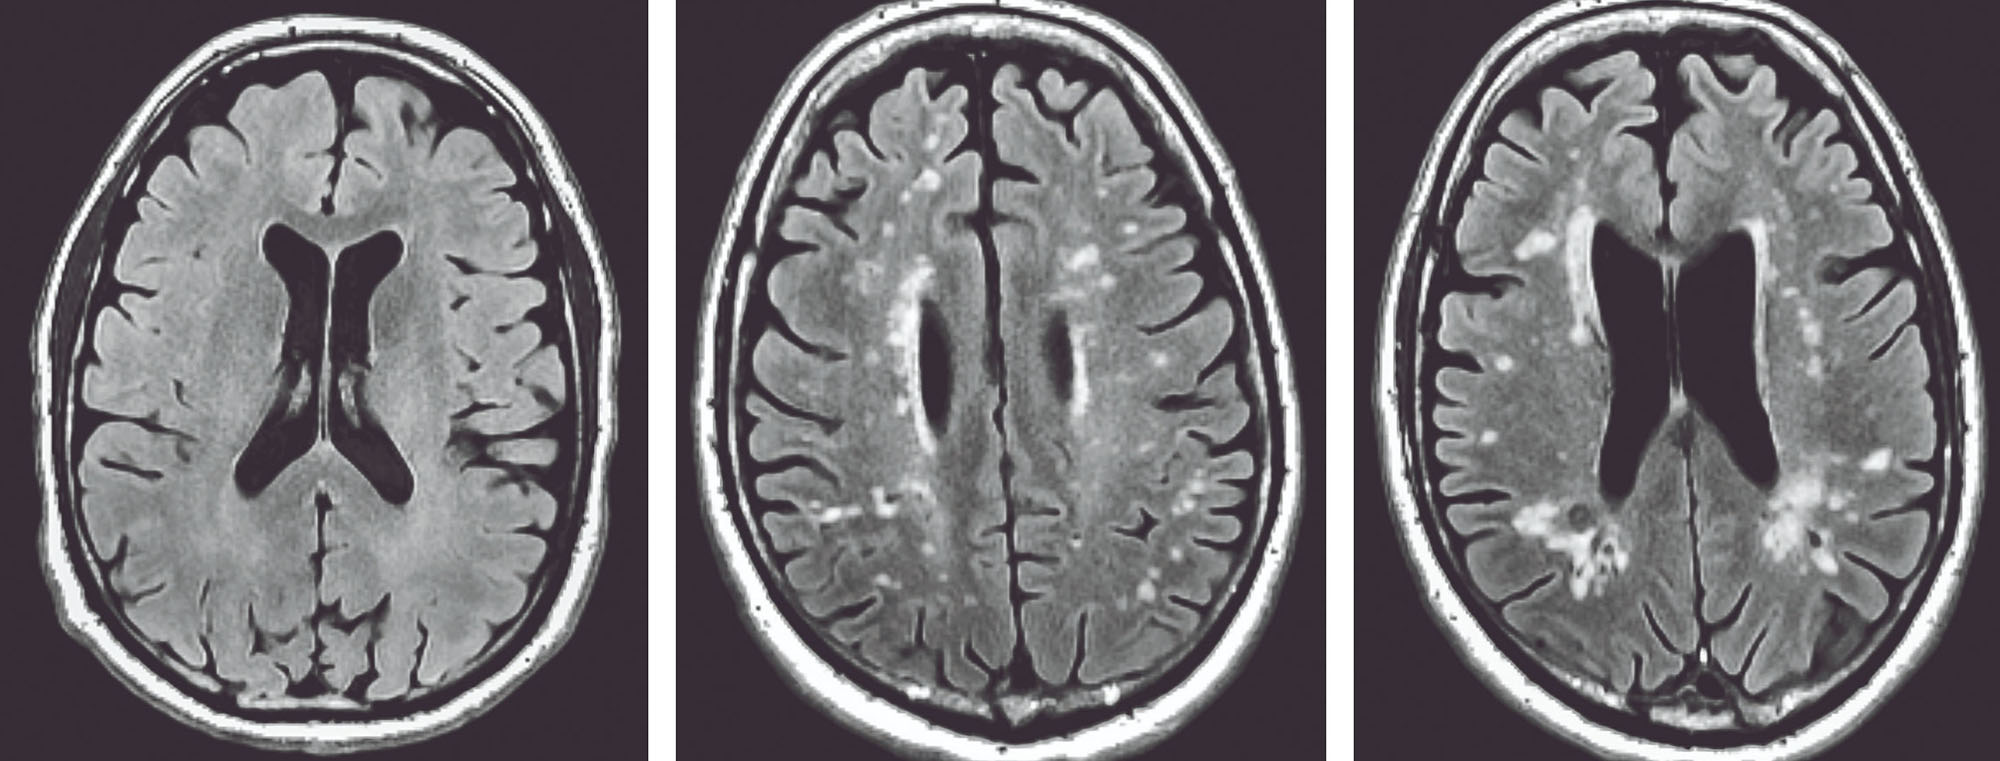

Following in Berenson’s groundbreaking footsteps, Carmichael and his collaborators at Tulane University, Mary Bird Perkins Cancer Center, and Pennington Biomedical looked at a subset of now middle-aged Bogalusa Heart Study participants who had elevated but still normal blood glucose levels as children and found that many of them have now developed brain lesions called white matter hyperintensities. These lesions are associated with cognitive decline and other poor health outcomes in much older adults.

“We see these white matter lesions in brain scans of people who are in their 70s, 80s, and 90s, and these are associated with poor outcomes such as Alzheimer’s disease, stroke, and also early mortality,” Carmichael said. “But the conventional wisdom was always that there should be very, very little, close to none, in patients in their 40s and 50s.”

three brain scans

Three Magnetic Resonance Imaging, or MRI, brain scans that show a healthy brain (left) and two with brain lesions called white matter hyperintensities (center and right) common in people in their 70s or older. These lesions, however, are less common for people in their 50s, the age of the study participants. People with more of these lesions are more likely to experience a number of health issues, from Alzheimer’s disease and stroke to falls and Parkinson’s disease.

– Credit: Owen Carmichael, LSU Pennington Biomedical Research Center